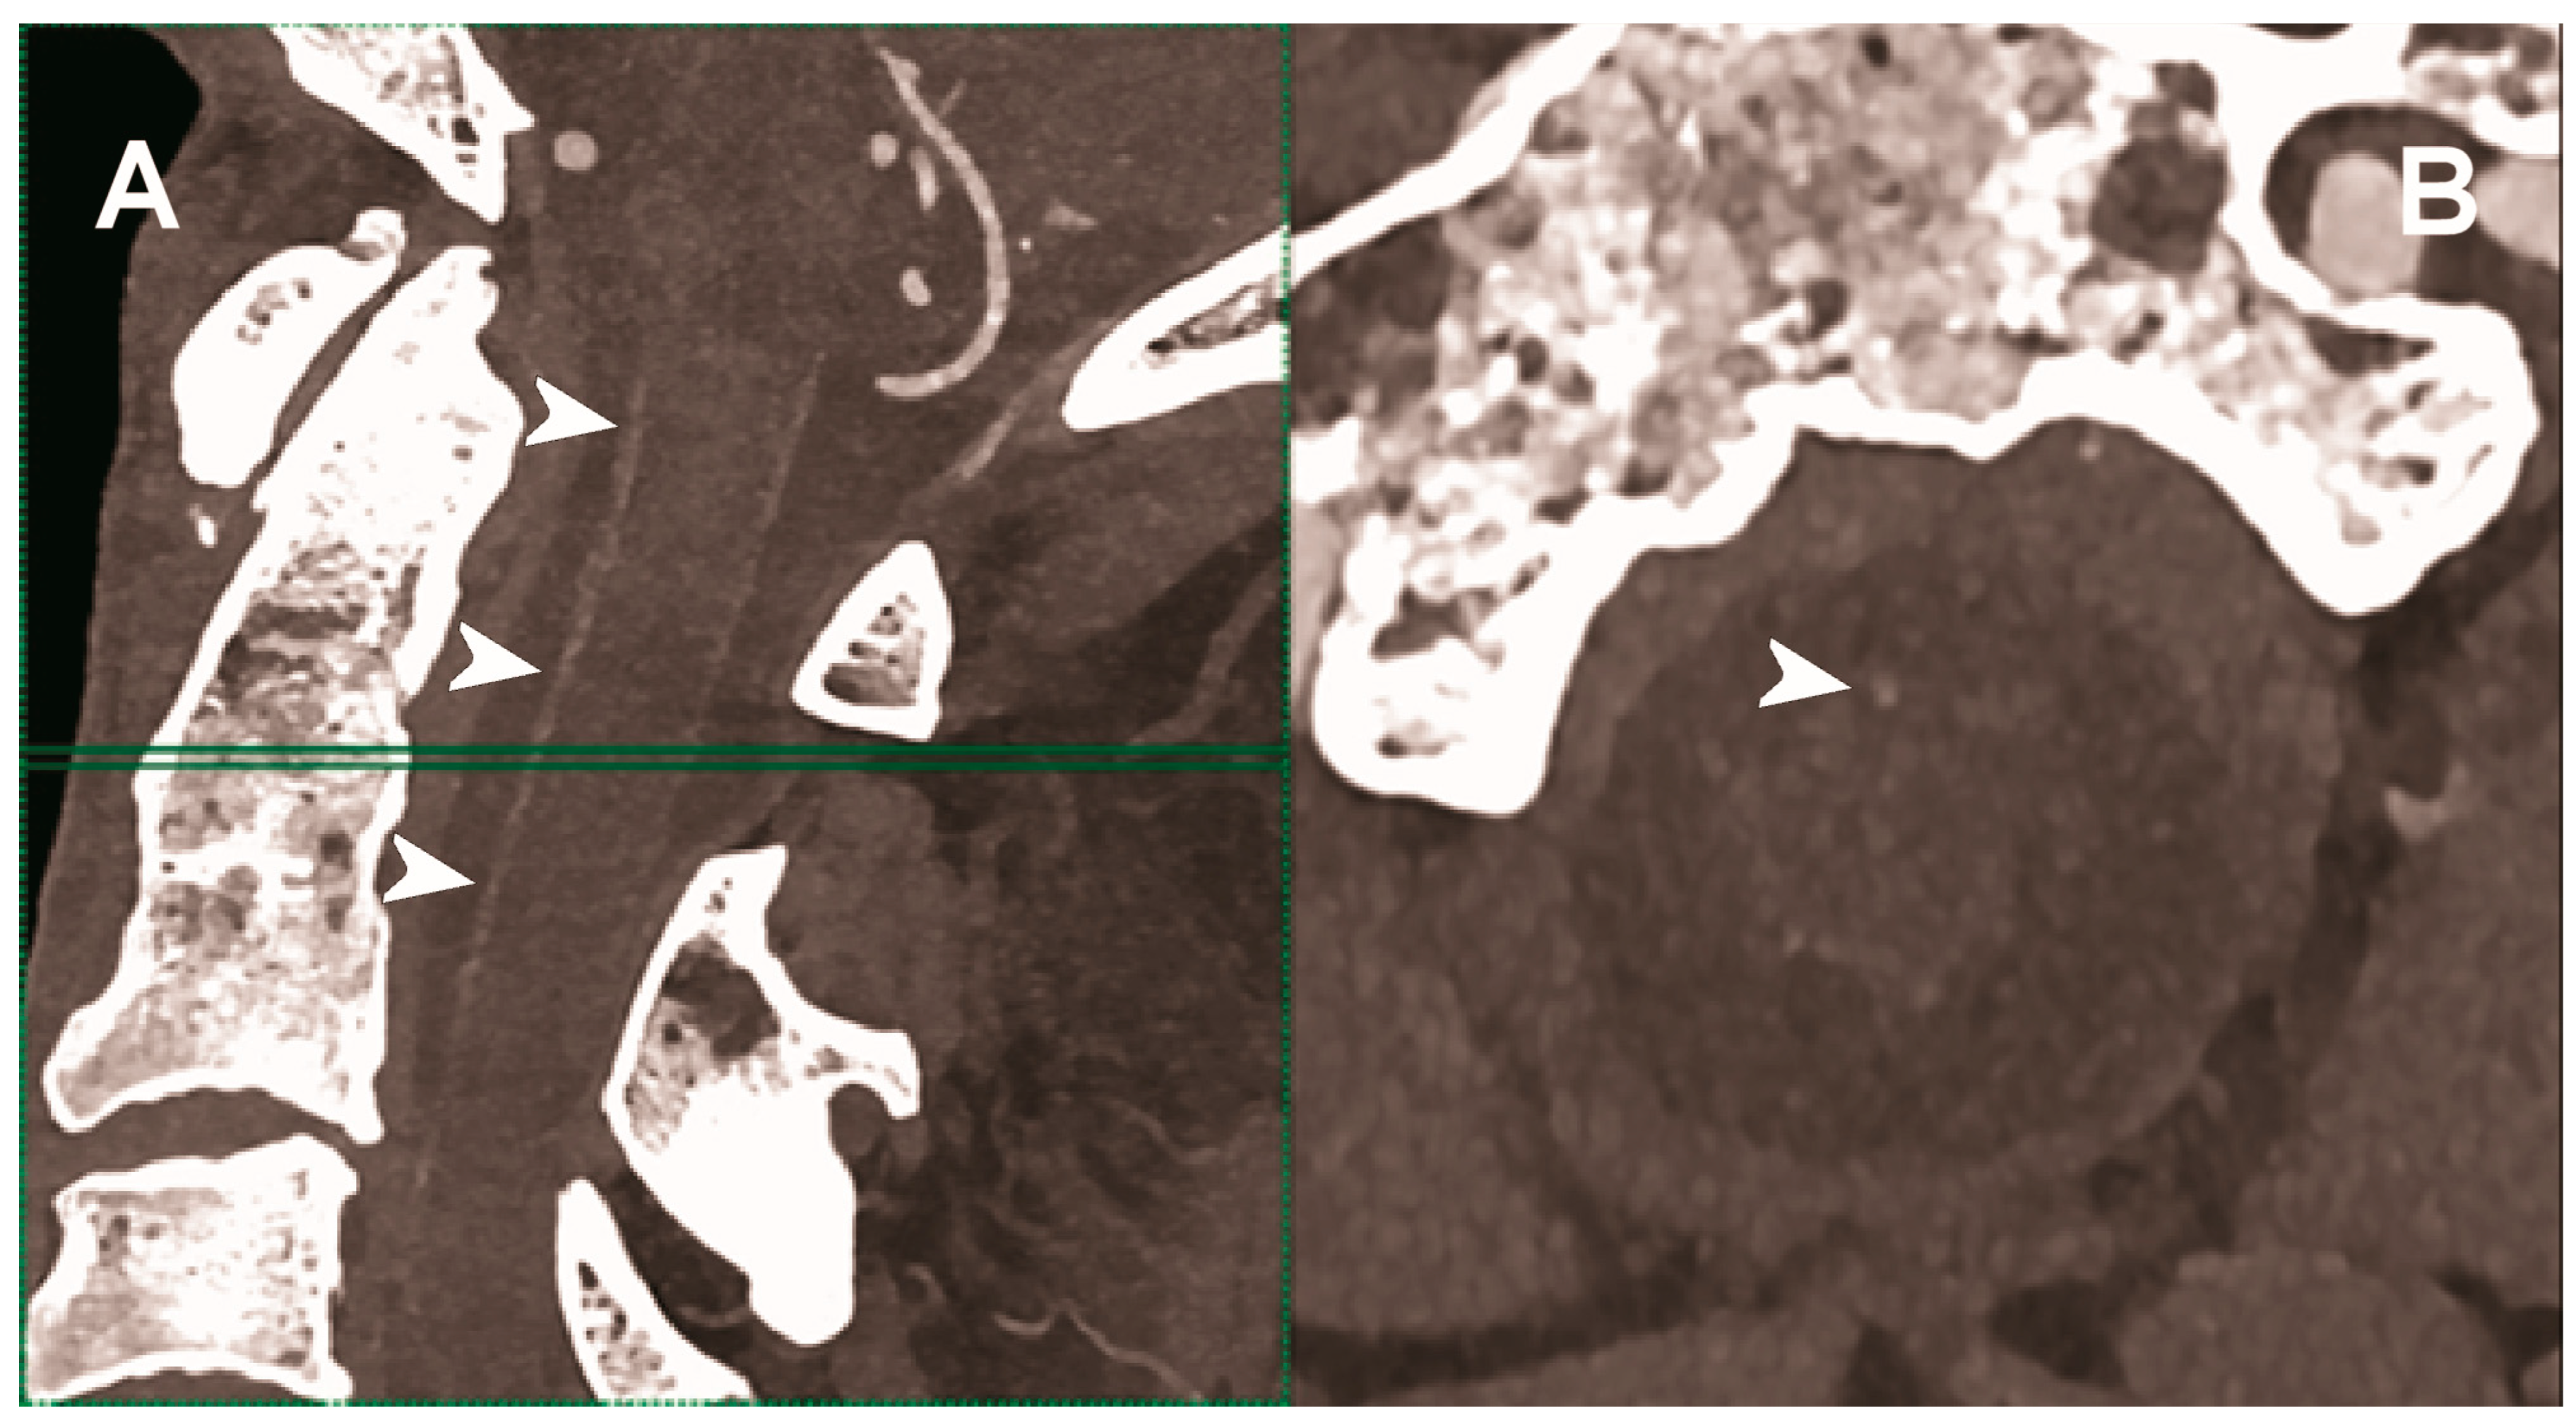

| Hetterich et al. 2014 [103] | Ex vivo (7 postmortem human carotid artery specimens). |

|

| Sartoretti et al. 2020 [104] | Ex vivo (carotid artery specimen of deceased male donor). | Improved lumen and plaque visualization and image noise with PCCT employing the multi-energy bin option in combination with tungsten as contrast media compared with the standard iodine. |

- Hetterich, H.; Willner, M.; Fill, S.; Herzen, J.; Bamberg, F.; Hipp, A.; Schüller, U.; Adam-Neumair, S.; Wirth, S.; Reiser, M.; et al. Phase-contrast CT: Qualitative and quantitative evaluation of atherosclerotic carotid artery plaque. Radiology 2014, 271, 870–878. [Google Scholar] [CrossRef] [PubMed]

- Sartoretti, T.; Eberhard, M.; Rüschoff, J.H.; Pietsch, H.; Jost, G.; Nowak, T.; Schmidt, B.; Flohr, T.; Euler, A.; Alkadhi, H. Photon-counting CT with tungsten as contrast medium: Experimental evidence of vessel lumen and plaque visualization. Atherosclerosis 2020, 310, 11–16. [Google Scholar] [CrossRef] [PubMed]